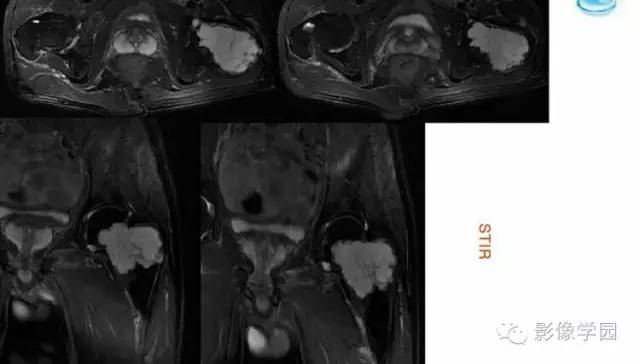

【病例】股骨软骨粘液样纤维瘤1例X线及MR影像表现